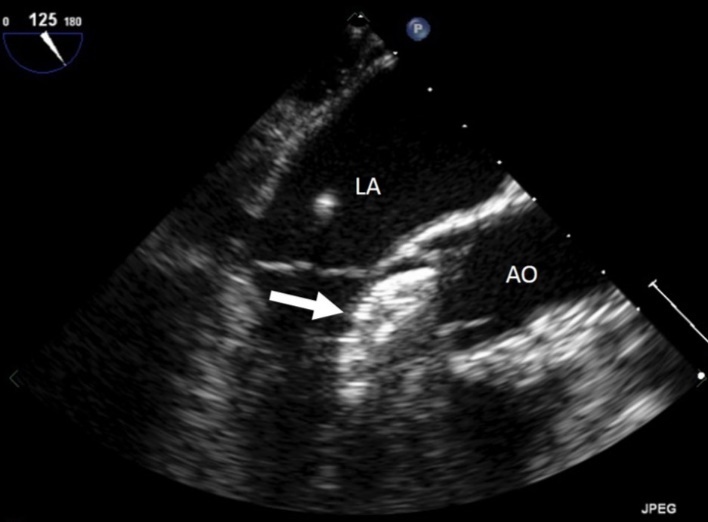

On examination, her heart rate was 71 beats per minute regular, blood pressure was 143/80 mm Hg, air saturation was 96% breathing ambient air and no fever. Jugular veins were not engorged. S1 and S2 were normal. There was a grade 3/6 ejection systolic murmur at right upper parasternal area. 24 hours ECG monitoring showed sinus rhythm. The neurological and pulmonary examination was normal. She underwent immediate transthoracic echocardiography and subcostal view showed a left-right shunt at the interatrial septum. Further evaluation revealed that the device embolized to the left ventricle and was lying in the left ventricular outflow tract with the distal extremity crossing the aortic ring. The device was displaced longitudinally with an important effect of stenosis. (Figure 1), (Figure 2). The entrapped device induced mechanical obstruction of the left ventricular outflow tract with a maximum/minimum gradients of 64/42 mmHg. The left ventricular function and size were normal. The mitral valve was normal with a minimal regurgitation. The right ventricle was mildly enlarged with normal function. The tricuspid valve function was normal. No pericardial effusion was detected. There was no gross thrombus deposition over the device in echography and no vegetation was detected anywhere.

Figure 1.Entraped Amplatzer ASD closure device in the left ventricular outflow tract. LA : left atrium, AO : aorta, arrow : ASD closure device.